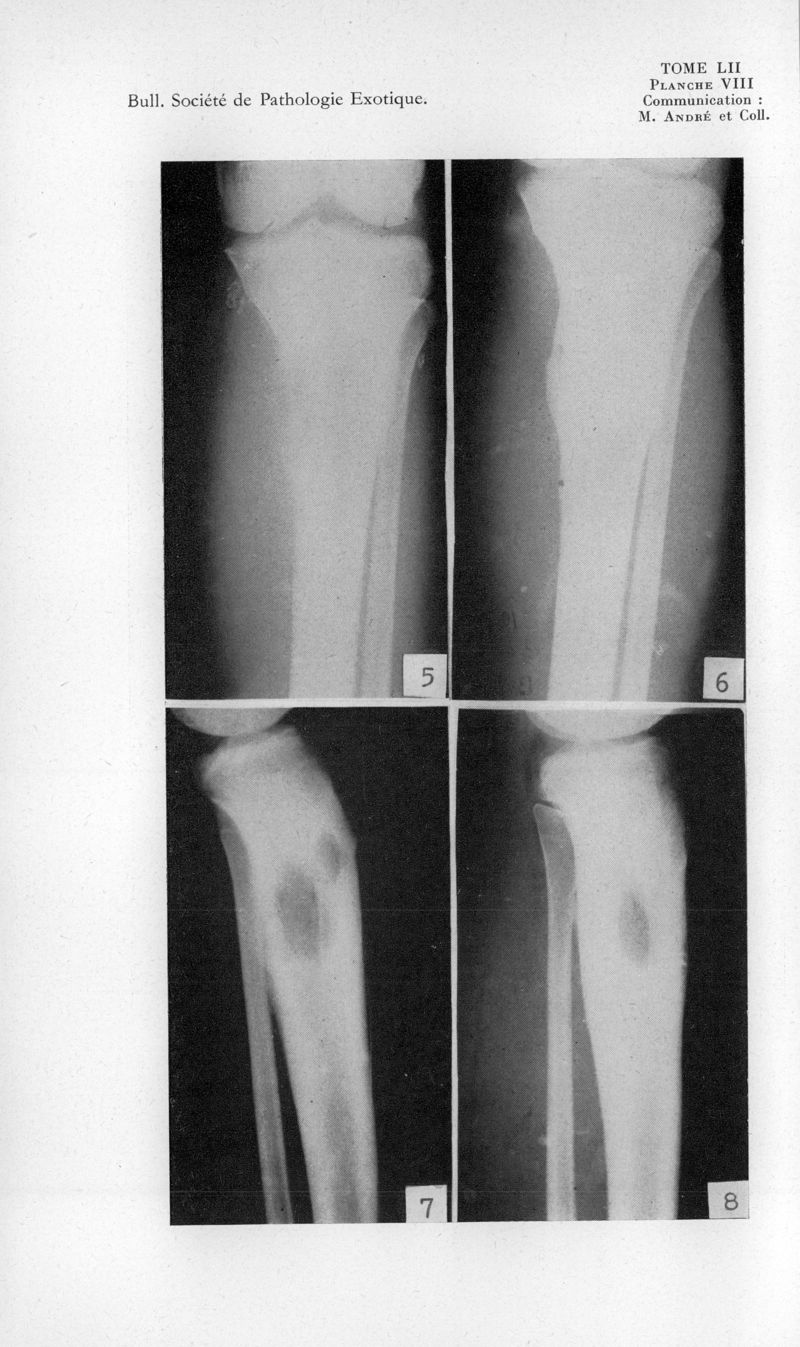

Bulletin de la Société de pathologie exotique et de ses filiales

1959, tome 52. - Paris : Masson, 1959.